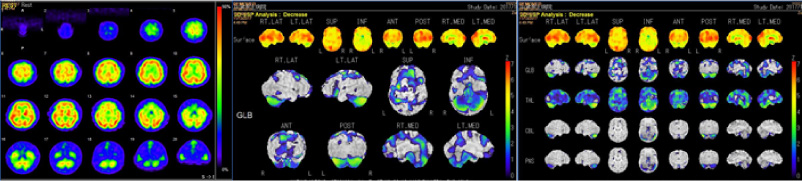

RI(核医学検査)

RI検査(核医学検査)は、ごく微量の放射性物質(ラジオアイソトープ:RI)を含む薬を用いて病気を診断する検査です。この放射性医薬品を注射、吸入などにより体内に取り込みます。体内に取り込まれると、特定の臓器(骨や腫瘍など)に集まりそこから放出される放射線(γ線)をガンマカメラで測定し、その分布を画像化します。

この検査の特徴は臓器の位置や大きさの他に機能が分かるというところです。

検査の種類

心筋血流シンチ 脳血流シンチ 骨シンチ 甲状腺シンチ 腫瘍シンチなど

骨シンチ

転移性骨腫瘍

狭心症

心筋シンチ

脊髄小脳変性症

アルツハイマー型認知症 脳血流シンチ

【当院では心筋シンチと脳血流シンチに特に力を入れています】